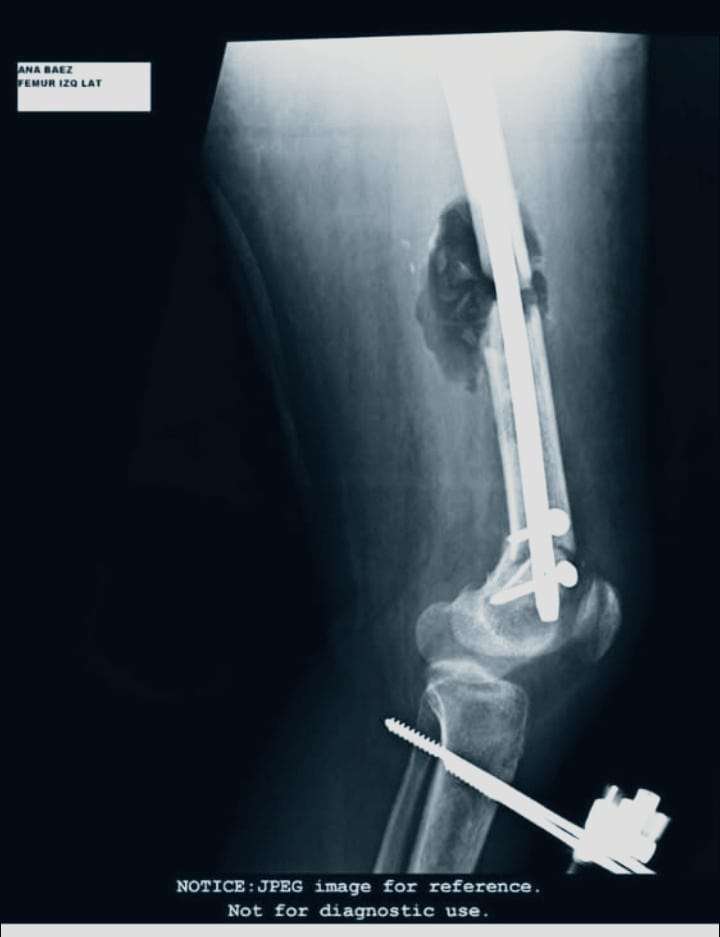

La afectada explicó que fue atropellada por una persona en estado de embriaguez, lo que le provocó múltiples lesiones de gravedad: la pérdida de una costilla y una pierna fracturada en siete partes, además de la ausencia de un hueso. A esto se suma una infección bacteriana severa (seudomona) que, asegura, alcanzó el hueso, causándole fiebre constante, dolores intensos y noches sin poder dormir.